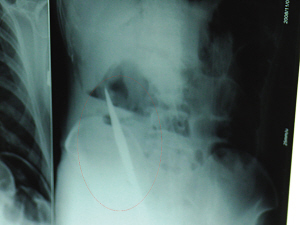

X光片上,尖刀清晰可見。

從男子體內取出的尖刀足足有19厘米長。

銅山一58歲男子因服毒被送到醫院搶救,可醫生采取搶救措施后卻發現效果不佳。后來經細致檢查,醫生有了個驚人的發現,該男子的體內竟然有一把尖刀,醫生通過手術將位于其腹部右側橫結腸下緣的尖刀取了出來。這把尖刀足足有19厘米長!據醫生推測,這把刀應該是從肛門推進體內的,不知男子為何想以如此殘酷的方式結束自己生命。由于搶救及時,該男子已暫時脫離危險。

6日上午,記者在徐州礦務集團總醫院重癥監護室見到了這名男子,目前他雖然已經恢復了意識,但還不能開口說話,需要呼吸機輔助呼吸。據醫生介紹,4日中午12時左右,這名男子因服毒輕生被緊急送到醫院進行搶救,之前,這名男子已經在當地鄉鎮醫院進行了近20小時的治療,但效果不佳。“病人被轉院到礦總院時已神志不清,血壓極低,處于休克狀態。”救護人員給男子洗胃、初步處理以后,發現男子呼吸急促,于是趕緊給他拍片檢查。結果讓所有的醫生大吃一驚,竟有一把尖狀異物橫在該男子腹腔內!當天下午5時30分,輕生男子被推上了手術臺。經過40多分鐘的手術,該男子腹腔被打開,手術醫生發現,男子體內的金屬狀異物竟然是一把長19厘米的尖刀!

醫生告訴記者,手術后,醫生在病人身上并未發現刀痕,最后,經過檢查發現,在該男子直腸處找到穿孔。醫生從醫學角度分析后認為,這把尖刀應該是從肛門插入直腸的。醫生說,因為病人搶救及時,尖刀并未傷及要害,所以暫時保住了性命,但后期可能會出現腹腔感染、AIDS、器官衰竭等多種并發癥。